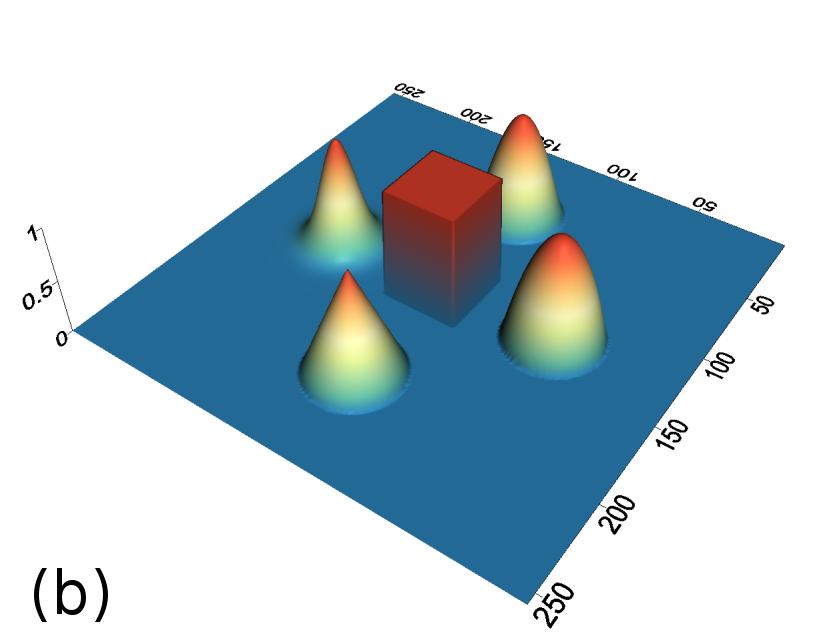

To test the proposed penalty in regularized tomographic reconstruction we designed an analytical phantom which consists of a smooth (two Gaussians and two parabolas) and piecewise-constant (one rectangle) functions (see Fig. 1).

To avoid of reconstructing on the same grid where projection data was generated (so-called reconstruction with “inverse crime” [16]), we used a higher resolution of the phantom on a isotropic pixel grid to generate projections with a strip kernel [1]. Then Poisson distributed noise was applied to the projection data, assuming an incoming beam intensity of 3 (photon count). Reconstructions were calculated on a isotropic pixel grid and with a linear projection model [1]. We used 90 projection angles in 180 degrees (assuming a parallel beam geometry) to reconstruct the phantom.

Reconstructed images are presented in Fig. 4. Since CGLS-TV- reconstruction might look more appealing than CGLS-EL we also show the surface representations of reconstructed images (see Fig. 5) and horizontal middle cross-sections (see Fig. 6).

One can notice that CGLS reconstruction is very noisy. CGLS-TV method better suppresses noise, however smooth features are strongly affected by the “staircasing” effect. CGLS-TV- method provides reconstruction with smoother features and CGLS-EL method resolves smooth features even better (e.g. cone-shaped parabola). Although CGLS-EL method performs very well for smooth objects one can notice the wave-like variations of intensity in the background and also at the top of the rectangle (see Fig. 6). This issue can be explained by the properties of our regularizer, in contrast to TV, our penalty does not seek the sparsest solution and does not penalize strongly (pushing to the constant value) a small intensity perturbations. The EL term tends to preserve all sharp edges while uniform noise is smoothed isotropically with the Laplacian. In Fig. 6 one can see that the CGLS-EL method provides better recovery of smooth features while slightly higher (compare to TV and TV-) perturbations visible in uniform areas (the top of the rectangle), however, the edges of the rectangle are defined sharper with the EL penalty.